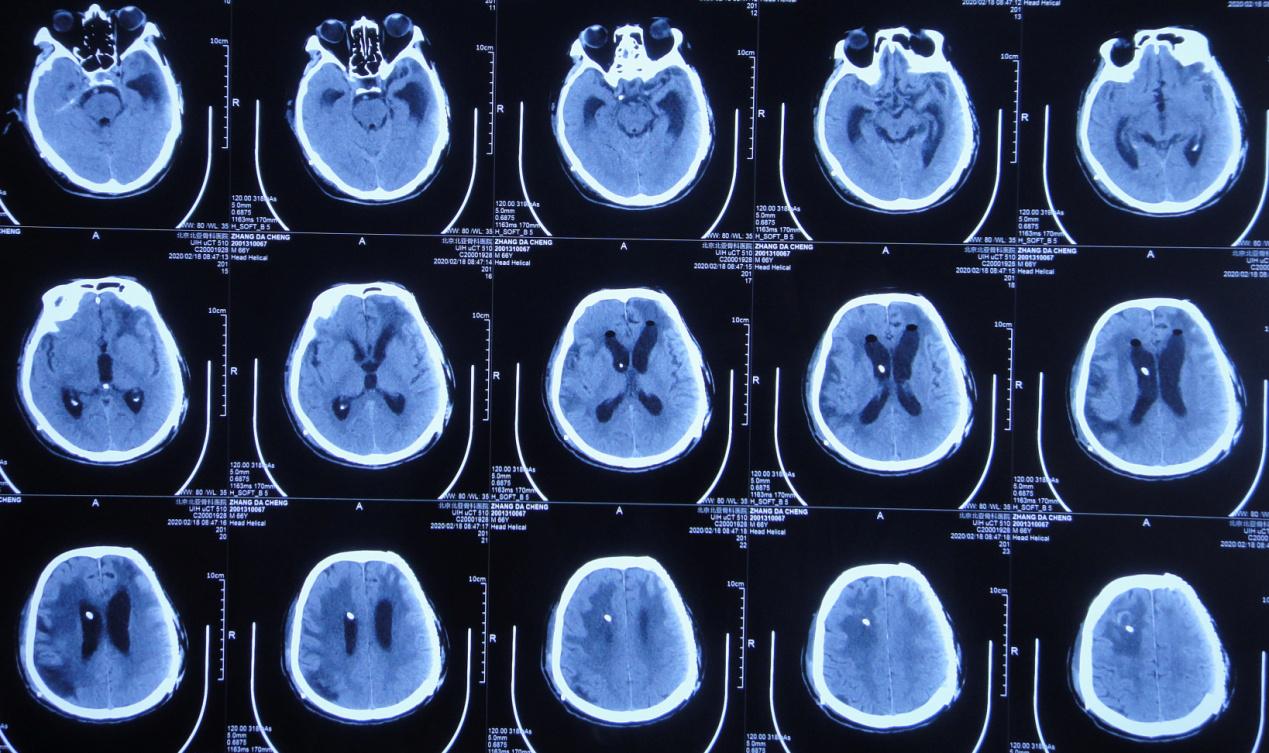

入院时:体温高达38.9℃,呈昏迷状态,疼痛刺激时四肢未见活动;颈稍抵抗,双下肢Babinski征未引出( 图-16 );头颅CT( 图-17 )示脑室腹腔分流术后改变,脑室扩张,脑室周围水肿。

图-17: 2020年1月31日头颅CT

入院第2天,即2020年2月1日行右侧脑室外引流术,术中拔除原脑室腹腔分流管,术后当日复查头颅CT( 图-18 )呈术后改变。

图-18: 2020年2月1日头颅CT术后

经过17天的治疗,于2020年2月18日行脑室腹壁外引流术,术后当日复查头颅CT( 图-21 )呈脑室引流术后改变,脑室较前缩小,脑室周围水肿减轻。

图-21: 2018年2月18日术后头颅CT

2020年4月27日,复查头颅CT( 图-23 )示脑室系统基本恢复正常。于2020年4月28日(即入院第88天,脑室外引流术第87天,脑室腹壁外引流术后69天)行脑室腹腔分流术,术后病情恢复良好。

图-23: 2020年4月27日头颅CT

经过李小勇脑脊液科98天的精心治疗,患者于2020年5月8日出院。出院前查头颅CT( 图-24 );出院时已能独立行走( 图-25 )。

图-24: 2020年5月7日出院前头颅CT